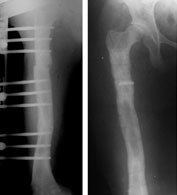

The final x-ray pictures just before fixator removal (left) and just after fixator removal (right).

The picture on the right is taken right after the fixator removal. The radiolucent shadow is the broken piece of threaded screw impacted in the bone. Also seen are the tracts left behind in the bone in the places where the schanz screws had been before removal. These tracts get filled up with new bone in about 3 weeks time. During this time we advise “careful weight bearing,” i.e. walk full weight-bearing with the aid of a crutch or a stick.